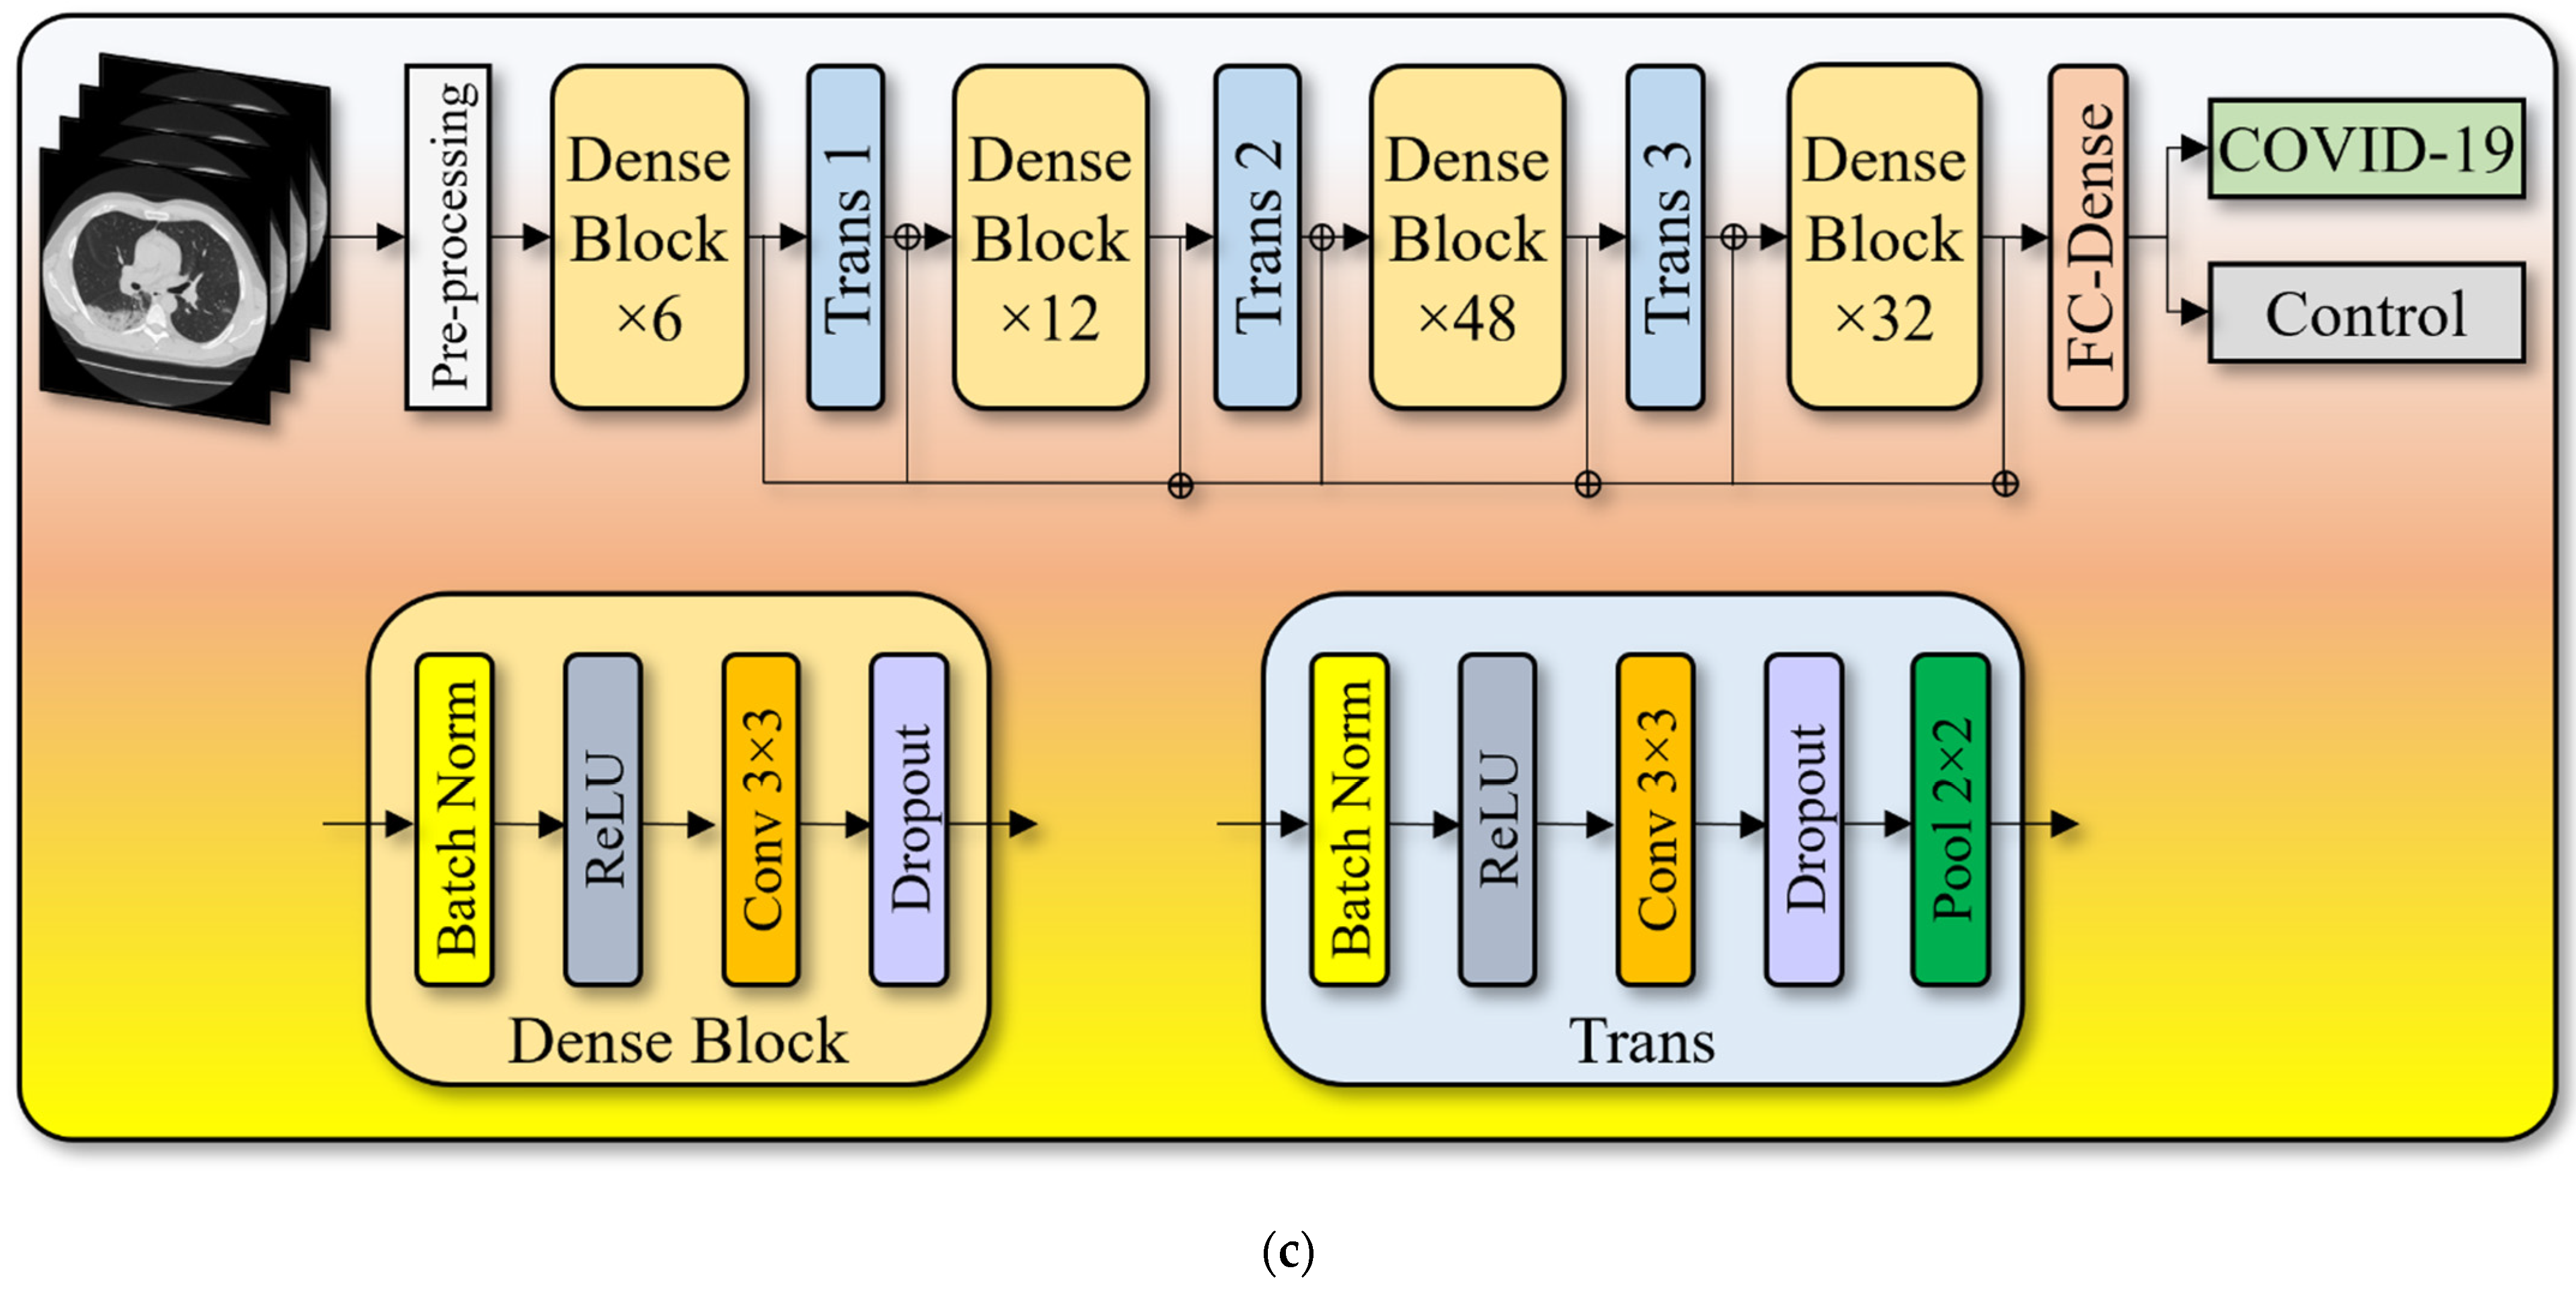

2.3. Artificial Intelligence Architecture

2.3.2. Dense Convolutional Network Architecture